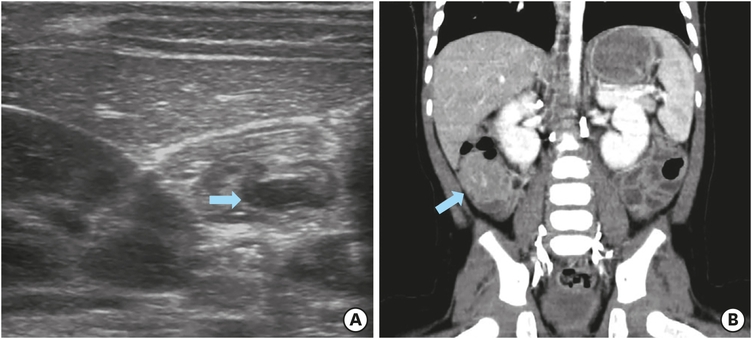

On the first day of hospitalization, formula feeding was started. There were no symptoms after the diet progressed. On the second day of admission, the patient became irritable and bloody stools recurred. Ultrasonography showed recurrence of intussusception and a second air reduction was performed. After successful decompression, the patient had a follow-up ultrasound the next day. On ultrasonography, ileocolic intussusception was re-developed in the right abdomen and 1.4 cm long low echoic focal eccentric wall thickening was observed in the distal part of intussuscipiens (Fig. 1A). This was the lesion thought to be the lead point. A third air reduction was performed for recurrent intussusception. After the patient was stabilized, abdominal computed tomography (CT) was performed to evaluate the lesion suspected as a lead point on ultrasound. On CT scan, the lesion appeared to be in the form of focal enhancing wall thickening with recurred ileocolic intussusception (Fig. 1B). There were no findings suggestive of Meckel's diverticulum or duplication cyst. The patient was diagnosed with intussusception with a lead point. The patient underwent exploratory laparoscopy. Laparoscopic reduction of intestine was performed for findings of intussusception. We used 3 mm laparoscopic instruments during surgical reduction of intussusception. Two graspers were mainly utilized during the procedure. We grasped the proximal ileum and cecum with laparoscopic graspers and gently pulled both ends apart. Care was taken not to injure the bowel during the procedure, both at the point where the bowels were grasped and around the intussusceptum. The serosal surface of the terminal ileum showed a dimpling spot and vague surrounding irregularity after successful reduction. Also, firmness of the bowel surrounding the dimpling spot was felt through the laparoscopic instruments. It was fairly obvious that there was a mass lesion within (Fig. 2A). In the intra-lumen of ileum, there was a solid, immobile mass-like lesion of 1 cm in size with central ulceration (Fig. 2B). The umbilical incision was extended craniocaudally and a wound protector was applied. The cecum and terminal ileum were mobilized and externalized through the umbilical incision. A firm, fixed mass was felt on the ileum wall 5 cm proximal to the ileoceceal valve and 4 cm segment of the surrounding ileum was resected. The ileal ends were anastomosed in end-to-end fashion with interrupted running sutures. The patient recovered without complications. He was discharged on the sixth day after surgery. Histopathological examination of the lesion revealed features of diffuse large B-cell lymphoma (Fig. 2C and D). We referred the patient to the Department of Pediatric Oncology for evaluation and initiation of chemotherapy treatment. This disease was classified as stage II germinal center B-cell like diffuse large B cell lymphoma. Patients and parents showed good adherence to treatment and followed recommendations of the oncologist.

Fig. 1

Ultrasonography and abdominal computed tomography findings for a 9-month-old boy, who was demonstrated to have recurrent intussusception: (A) Ultrasonography revealing recurred ileocolic intussusception with a lead point, an eccentric low echoic thickening (arrow) in the distal part of intussuscipiens. (B) Coronal abdominal computed tomography showing a focal enhancing wall thickening with recurred ileocolic intussusception (arrow). This focal enhancing lesion was thought to be the lead point.